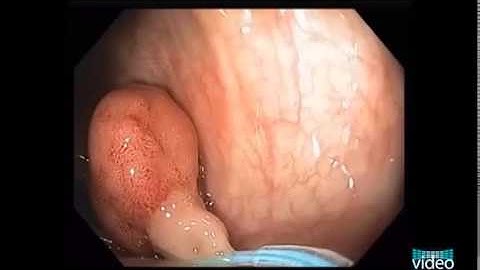

Step-by-Step Polypectomy of a Large Antral Polyp Using ENDOLOOP™, Hot Snare & Hemoclips